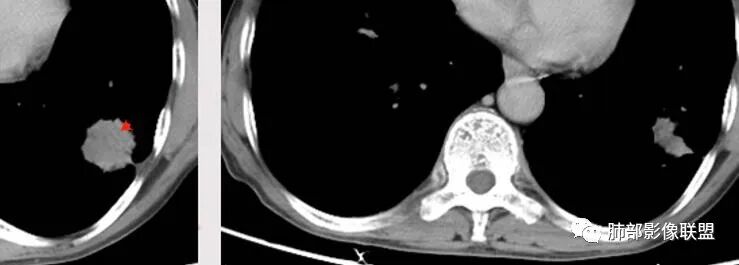

老年男性,肺气肿背景,结核病史。右肺下叶病灶,分叶不明显,局部可疑栽赃,毛刺略呈毛刷感,远端阻塞性肺炎改变,轻微强化,走行血管僵硬,湖泊样坏死,考虑鳞癌。左肺病灶边缘有分叶、毛刺及胸膜牵拉的恶性征象,也有平直收缩的良性征象,可疑卫星灶,这类良恶征象都有判断比较纠结,常规思路:炎性放前边,腺癌待排。

临床病史很长,背痛9年可能与左侧胸膜炎有关。两上肺陈旧性结核伴肺气肿没有问题。左下肺病灶,分叶毛刺、胸膜凹陷、指状凸起,增强轻度强化,腺癌问题不大。右侧附加题有些困难,病灶内血管显影,不像结核的表现,先把结核否掉?鳞癌和慢性脓肿的鉴别:支持良性的征像,低密度区内也有细小血管影,不像鳞癌坏死?与胸膜关系整体还是比较和谐,边缘还算光整,毛刺都在远端,不支持慢性脓肿的的地方,周围支气管管壁都很干净。恶性征像,与支气管的关系图片给的不够。坏死边缘不光整,有些浅分叶。总体,我觉得坏死区血管的存在更有价值,验证一下,右侧首先考虑慢性脓肿。

老年男性,结核、慢性病史,肺气肿背景,右肺胸膜下肿块影,边界清晰,边缘膨隆,中度环形强化,内见边界清晰坏死区,并见部分强化小血管,鳞癌破坏力强,而且病灶一侧支气管受推移,首先考虑右肺结核,鉴别鳞癌,左肺考虑腺癌,胸膜牵拉,膨隆生长,边缘毛刺样,潜在分叶。

小兜:

老年男性,既往肺结核病史。肺气肿背景,可见钙化灶及条索影。右肺下叶胸膜类圆形占位,边界清晰,内部可见边界清晰的坏死区,轻度强化,考虑为结核可能;左肺下叶结节,可见分叶,毛刺,胸膜牵拉,增强可见强化,考虑为恶性,腺癌可能。

大家说说右下叶病灶有啥特点?与左肺病灶有啥差异?

左边毛刺多,毛糙,收缩力大,胸膜牵拉。右边坏死多,边缘光滑,毛刺少

右大、左小

右侧光滑一些,左侧毛刺明显一些

1.左侧分叶深一些

2.右侧糊墙

左侧胸膜凹陷

3.左侧支气管显示欠佳,似乎在门口堵塞

右侧支气管门口堵塞,有推移迹象

4.右侧坏死明显,内部囊变坏死边缘部分清楚、部分不清

左侧坏死不明显